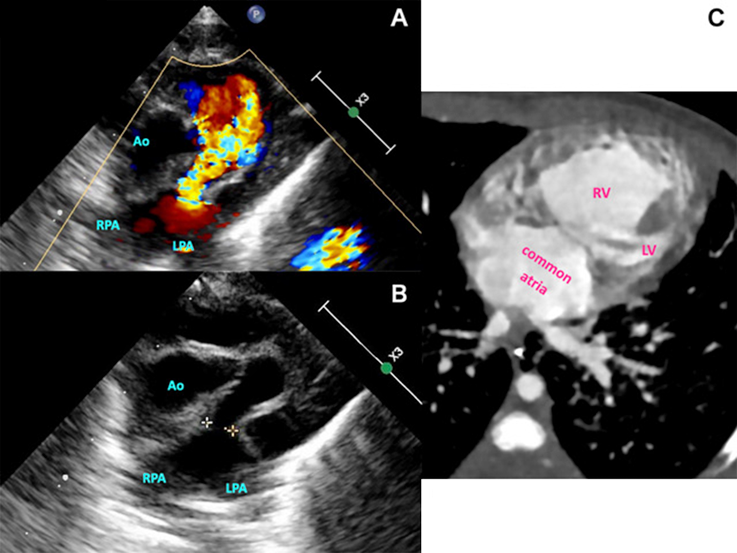

A female neonate was born at 38 weeks’ gestation weighing 2.8 kg and diagnosed as APVS, uAVSD with a small left ventricle, and left isomerism with interruption of the inferior vena cava (Fig. 1). She was intubated immediately after birth due to respiratory distress. The PAs are dilated (PA index, 1,354 mm2/m2) compressing the airway. On day 27, she underwent division of the pulmonary trunk, plication of the bilateral PAs, and construction of a modified Blalock–Taussig shunt (a 3.5 mm GORE-TEX© graft). She could not be weaned off cardiopulmonary bypass due to pulmonary hypoperfusion even after revision to a 4-mm shunt; hence, we completed the operation with extracorporeal membranous oxygenation (ECMO) support. On the first postoperative day (POD), her pulmonary perfusion improved, and she was able to come off ECMO successfully. We placed three clips onto the shunt graft to regulate pulmonary blood flow across it; her oxygen saturation was over 90% at that time, suggesting pulmonary overcirculation. The chest was closed on the 9th POD. She was extubated on the 15th POD. Catheter intervention was performed to increase pulmonary blood flow by ballooning out the clips on the 64th POD; by that time, hypoxemia had progressed gradually (Fig. 2). Her oxygen saturation rose from 70% to 89% subsequent to the interventional procedure, while she had a sign of cardiac failure with excessive pulmonary blood flow which necessitated controlled ventilation for a few months. Catheter examination at 6 months of age revealed that her ventricular end-diastolic pressure was 7 mmHg, mean PA pressure 14 mmHg, Qp/Qs 1.54, pulmonary vascular resistance 1.66 U·m2, and cardiac index 3.71 L/min/m2. Her serum brain natriuretic peptide was slightly elevated (102.6 pg/mL) prior to discharge from the hospital. Her body weight gain was acceptable (approximately +13 g/day). Finally, she was discharged home at 7 months of age. The palliation of the second stage was planned around 1 year old. One month later, however, she died of unknown causes despite having been transferred to our institution and received cardiopulmonary resuscitation.

Fig. 1 Echocardiography showing the absence of the pulmonary valve with severe regurgitation (A, B). Computed tomography showing unbalanced atrioventricular septal defect with a small left ventricle and a single atrial cavity (C). Ao, aorta; LPA, left PA; LV, left ventricle; RPA, right PA; RV, right ventricle.